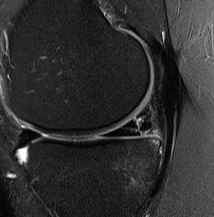

Signs of bucket handle tear meniscus

1. Double PCL sign

- medial Meniscus

2. Absent bow tie sign

- should see bow tie image on 2 consecutive sagittal slices of 5 mm

3. Fragment in notch sign

4. Anterior flipped meniscal sign

- torn fragment flips over the anterior horn of the affected meniscus

5. Truncated meniscus